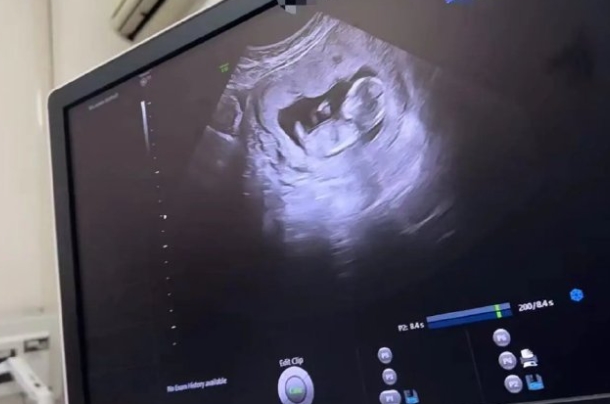

最近在孕妈群里总能看到这样的讨论:「昨天做NT看到宝宝的小鸡图了」「12周就能知道性别了吧?」。作为经历过两次产检的过来人,今天咱们就掰开揉碎了聊聊,这个让准爸妈们又期待又困惑的NT检查到底藏着哪些门道。一、NT检查的正确打开方式孕12周左右的NT检查全称「颈项透明层扫描」,说白了就是用B超测量胎儿脖子后面的液体厚度。这个数值要是超过2.5毫米,医生就会建议做进一步检查。北京妇产医院2022年的数